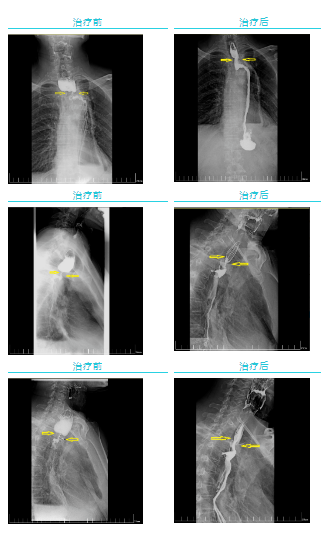

經(jīng)過一個周期的放療,李先生明顯感受好多了,可以正常吃飯喝水。食管鋇餐造影顯示,食管吻合口區(qū)腫塊明顯縮小,食管狹窄減輕。